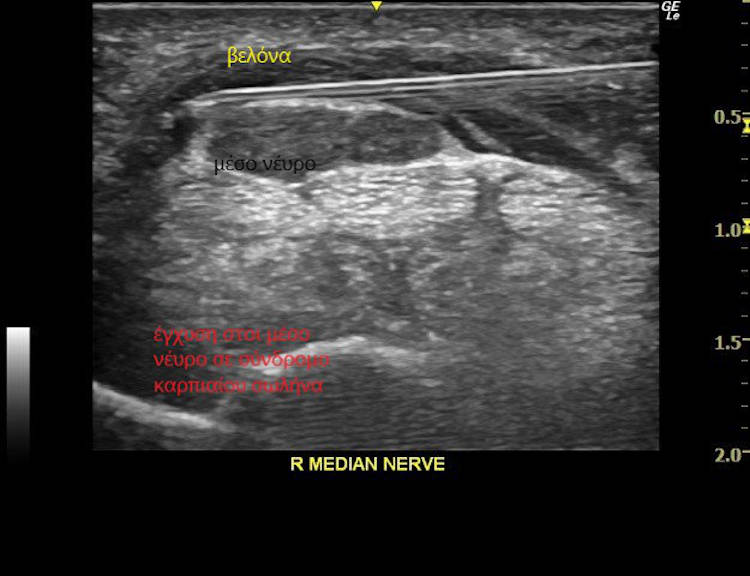

Ο υπερηχοφραφικός έλεγχος διενεργείται με έγχρωμο υπέρηχο τελευταίας γενιάς (ugeo samsung), με τρίπλεξ, ντόπλερ, ελαστογραφία για διάγνωση παθήσεων μυών, συνδέσμων και άλλων μαλακών μορίων όπως παραμορφώσεις της δομής τους (φλεγμονές, κυστικές συλλογές), περιλαμβάνεται ειδικό λογισμικό για καθοδηγούμενες εγχύσεις , ώστε η βελόνα να φτάνει με απόλυτη ακρίβεια στο σημείο στόχευσης,